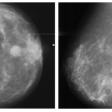

Mammography’s performance suffers when imaging dense breasts, with its sensitivity decreased by around 40% when scanning extremely dense breasts. This means that many cancers may be underdiagnosed in these women, with lower prognosis in women with distant or unstaged cancers.

In the U.S., the U.S. Food and Drug Administration (FDA) enacted a federal mandate requiring imaging facilities to disclose breast density information to women. The American College of Radiology (ACR) categorizes breast density from A through D, with A indicating nearly all fatty tissue and D meaning extreme density. The ACR also recommends MRI for women with dense breasts.

The study included data collected from 200 women with breast densities categorized as ACR C or D, indicating heterogeneously and extremely dense breasts, respectively.